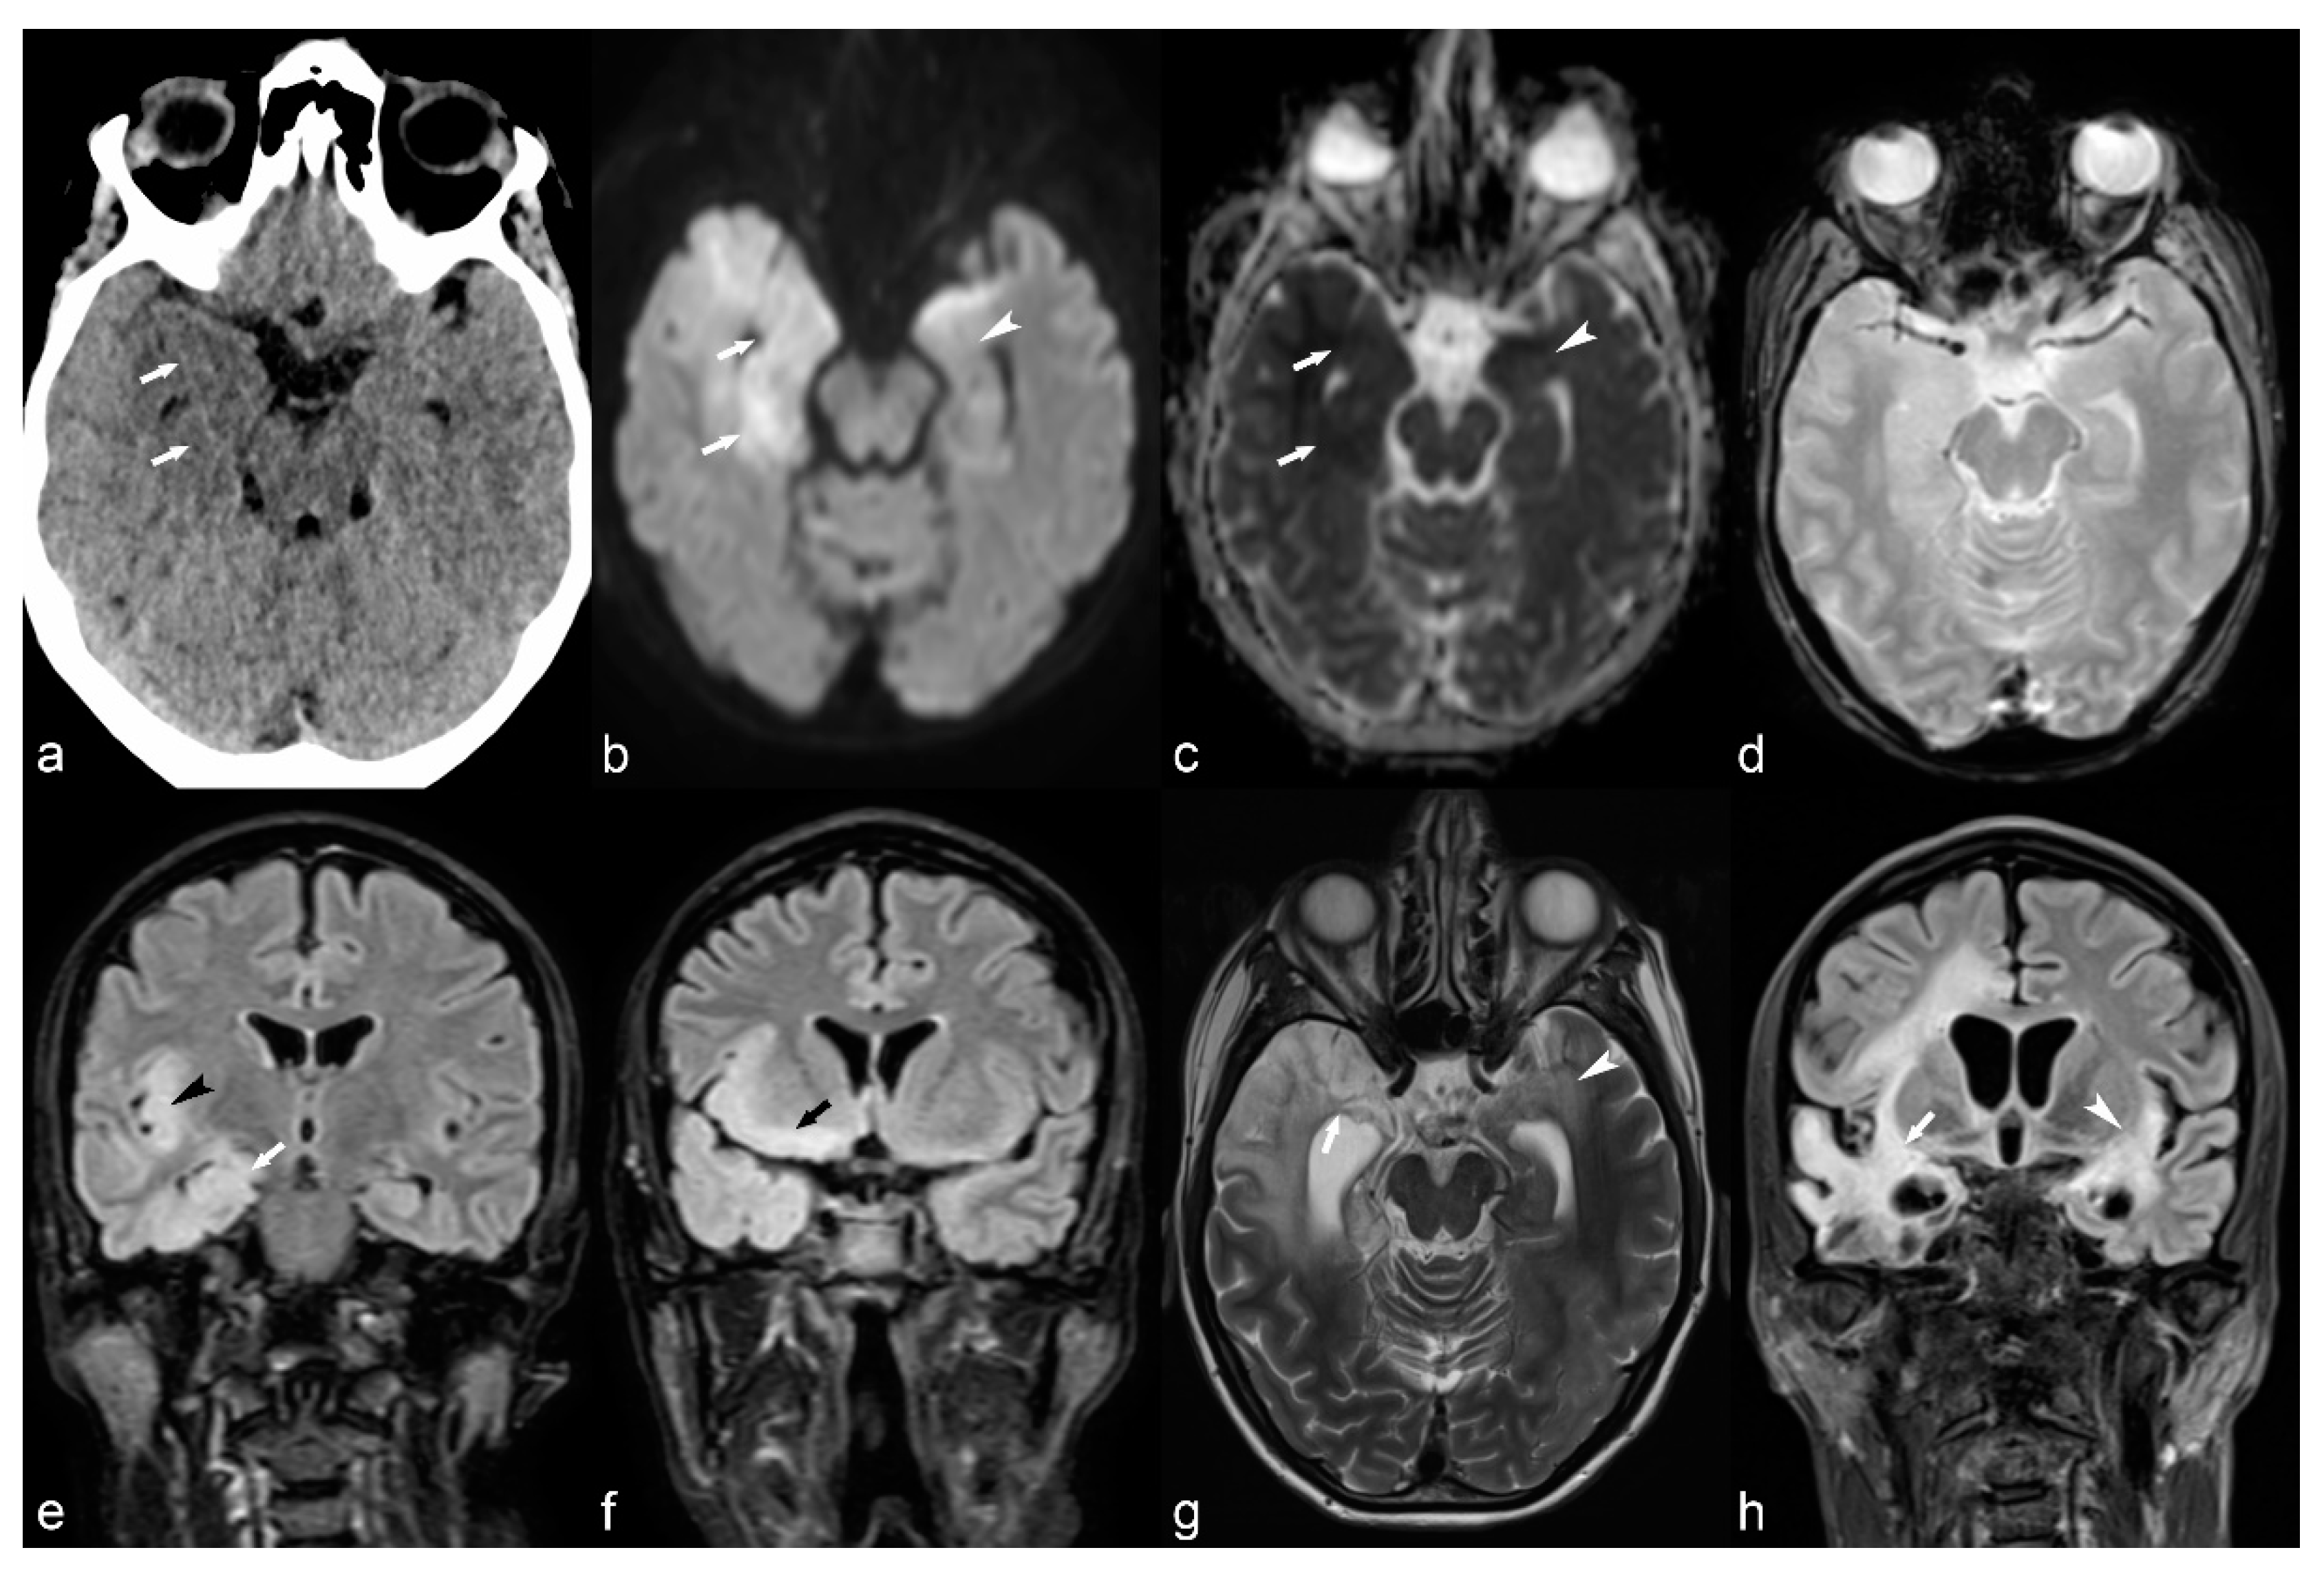

4.7. Gliotic Scars

Destructive brain lesions involving cortex due to different types of insults, more commonly ischemia, trauma or infection, can result in porencephaly, encephalomalacia, ulegyria, gliosis and secondary epilepsy. These insults can occur anytime during life, from the antenatal period to late adulthood and the severity of clinical manifestation is usually related to the severity of volume loss, the location of the lesions near eloquent areas of the brain, as well the time when the insult occurred. Cerebrovascular disease is the most common cause of acquired epilepsy in western countries, affecting mostly older patients [87]. The presence of blood products in the brain, known as hemosiderosis, is considered highly epileptogenic [88], while an increased risk for seizures has been observed as a sequela of meningoencephalitis [87]. In addition to volume loss, CT demonstrates low attenuation lesions and MRI shows hyperintense lesions on T2WI and FLAIR, and hypointensity on T1WI, reflecting gliosis (Figure 10 and Figure 11). Hemosiderosis is depicted as low signal lining the brain surface on T2 GRE or SWI images.

Figure 10.

20-year-old female with epilepsy. Axial T2 weighted (a) and coronal FLAIR (b) images show irregularity of the contour of the left lateral ventricle with ex vacuo dilatation, hyperintensity and paucity of periventricular white matter (arrowhead) in the frontal region suggestive of sequalae of perinatal insult i.e., periventricular leukomalacia.

Figure 11.

35-year-old woman with herpes encephalitis. Non-contrast CT (a) shows low attenuation in the right mesial temporal region (white arrows). DWI b1000 (b) and ADC map (c) confirm bilateral but asymmetrical restricted diffusion in the mesial temporal areas (white arrows and arrowhead). No haemorrhage is identified on T2* (d). There are signal abnormalities on FLAIR (e,f), most pronounced in the right mesial temporal lobe (white arrow), right insula (black arrowhead) and right frontal lobe (black arrow). MRI performed 2 months later (g,h) shows bilateral areas of encephalomalacia (white arrows and arrowhead), more pronounced on the right, despite treatment.